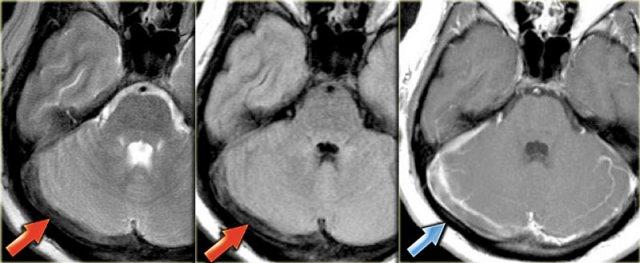

Hình ảnh bên trái là chuỗi xung T2W với tín hiệu trống dòng chảy bình thường ở xoang sigma phải và tĩnh mạch cảnh trong phải (mũi tên xanh dương).

Bên trái có tín hiệu cao bất thường là kết quả của huyết khối (mũi tên đỏ).

Các hình ảnh bên trái cho thấy tín hiệu cao bất thường trên chuỗi xung T1W do huyết khối.

Huyết khối lan rộng từ các tĩnh mạch não sâu và xoang thẳng đến xoang ngang và xoang sigma bên phải.

Lưu ý tín hiệu trống dòng chảy bình thường ở xoang ngang trái trên hình dưới bên phải.